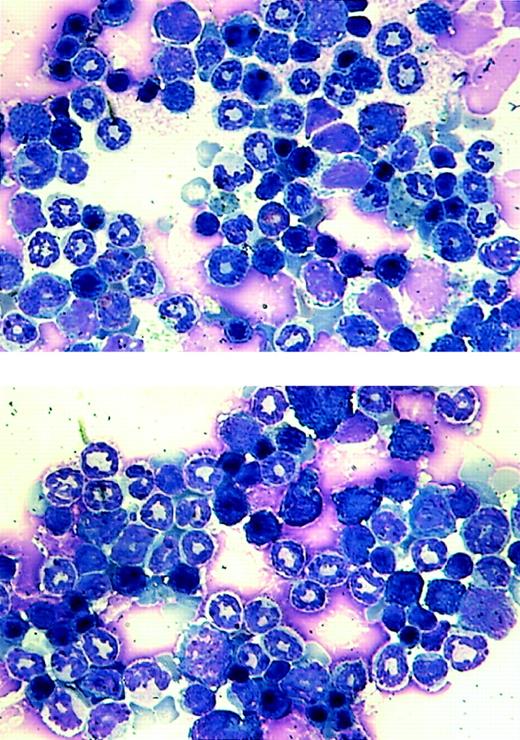

Our goal was to investigate the effect of AML1-ETO on hematopoiesis and its potential role in leukemogenesis. Because of the lethal effect of AML1-ETO on embryogenesis, we used the tet-off inducible system of gene expression. We observed adult double-positive mice that express AML1-ETO to study their hematopoiesis. These mice exhibited no outward signs of illness. Their coat appeared normal, and their level of activity was consistent with that of wild-type mice. We performed blood smears and differential counts of the blood from these mice. In all of the founder lines, the differential blood counts were normal (Table 1). We then used bone marrow cells from founder lines #7 and #8 to perform in vitro CFU assays. The numbers of different colonies observed for both double-positive and wild-type mice were approximately the same (Table1). These mice showed no abnormal hematopoiesis. CFU assays were also performed in which cells isolated from the same MMTV-tTA/AML1-ETO double-positive mice were plated in the presence or absence of tetracycline. No difference was observed in number or type of colonies generated (data not shown). Total RNA was then harvested from colonies from the CFU assay for founder line #8 and analyzed by Northern blot analysis. A similar level of AML1-ETO expression is seen in both the bone marrow of double-positive mice and colonies derived from the bone marrow of double-positive mice (Figure6). Bone marrow cells were also analyzed for their morphology (Figure 7). No significant difference can be observed between bone marrow samples from the control and AML1-ETO–expressing mice.

Morphological analysis of bone marrow cells from the transgenic mice.

Bone marrow samples were prepared from a wild-type littermate (top panel) and an MMTV-tTA and pUHD–AML1-ETO double-positive mouse and stained with Wright-Giemsa solution.